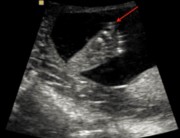

این تصویر نمونه ای از بررسی جنین در هفته 21 بارداری است. می توانید به راحتی پیشانی، بینی (فلش قرمز)، لب ها و چانه (فلش سبز)، پس گردن و بخشی از قفسه سینه را شناسایی کنید.